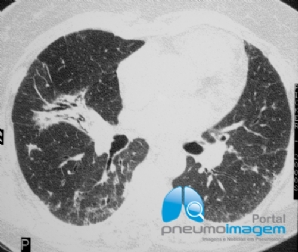

CASO CLÍNICO #52

Paciente do sexo feminino, 46 anos, submetida a transplante de medula óssea há 2 meses, apresenta-se com dispneia, tosse seca e dessaturação. Qual o provável diagnóstico? Deixe seus comentários abaixo! ***** A 46-year-old female patient who underwent bone ma...